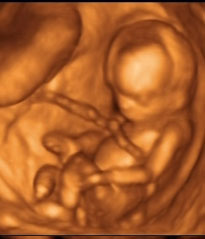

Három kicsi angyalkánk (Három kisbaba, akik nem születhettek meg)

Született: Sajnos nincs,

Meghalt: 2006. április, 2007 április, 2009 augusztus

Három kicsi angyalkánk